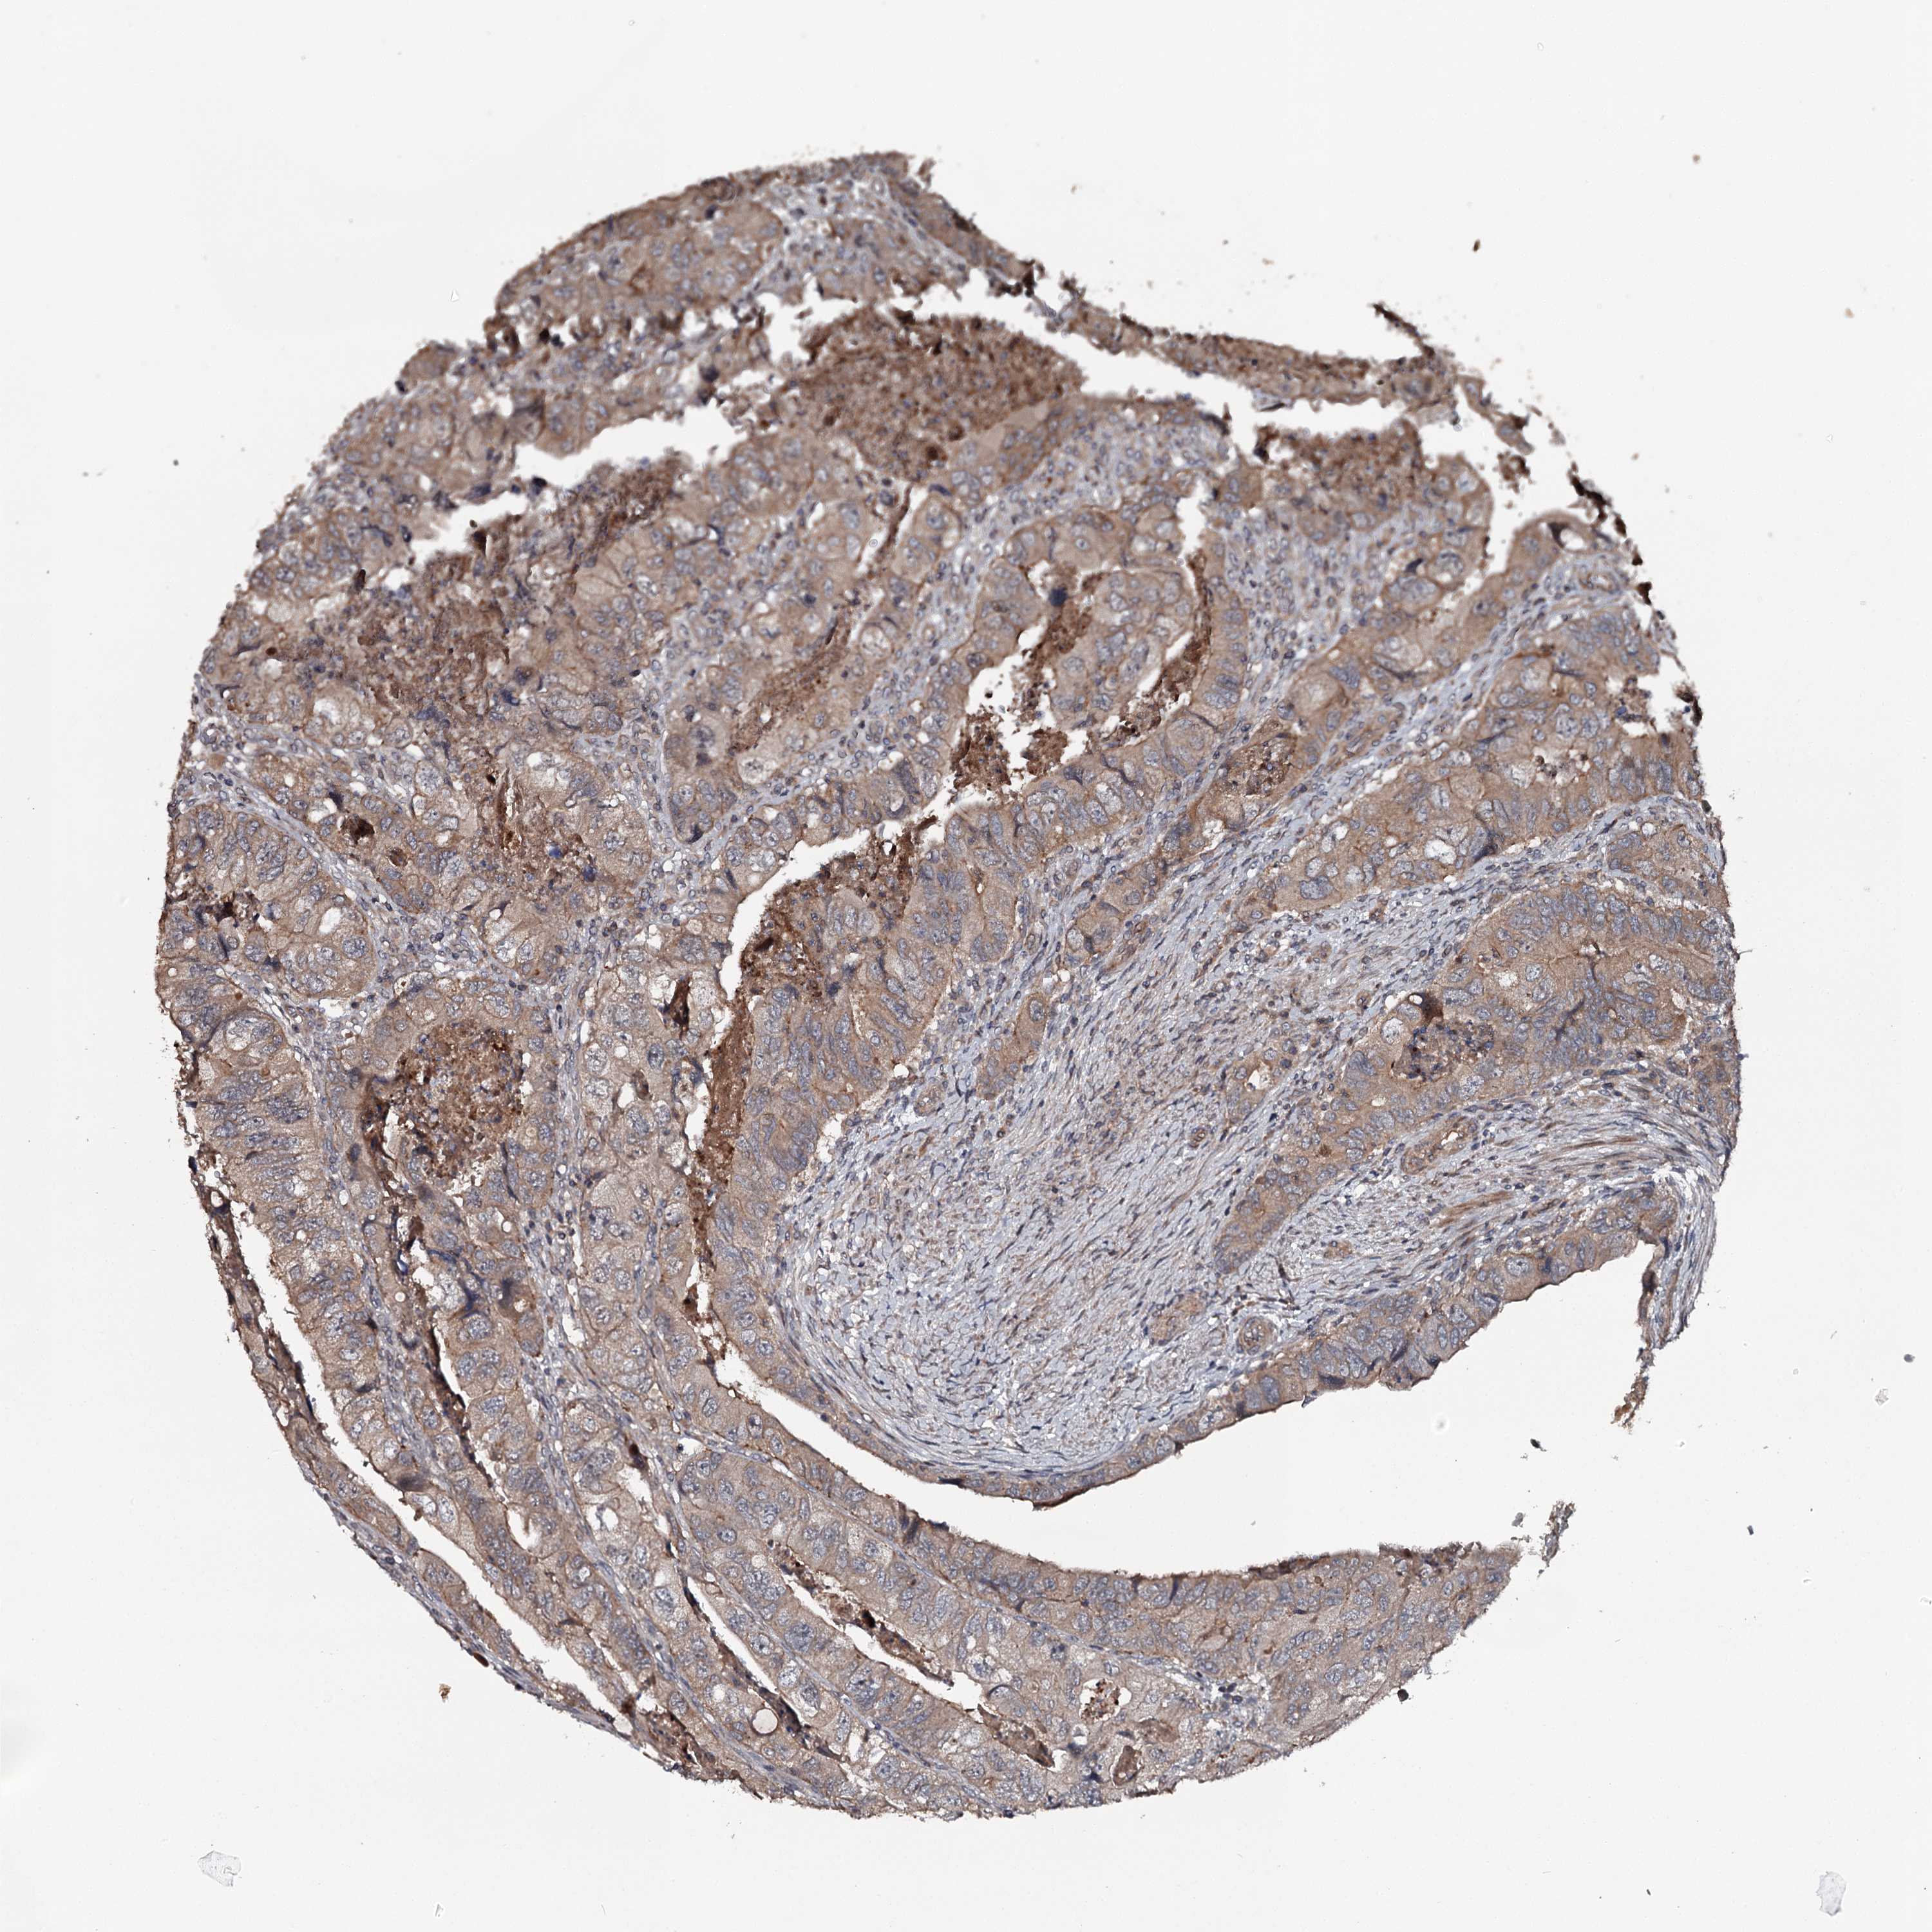

Colorectal cancer

Human cancer